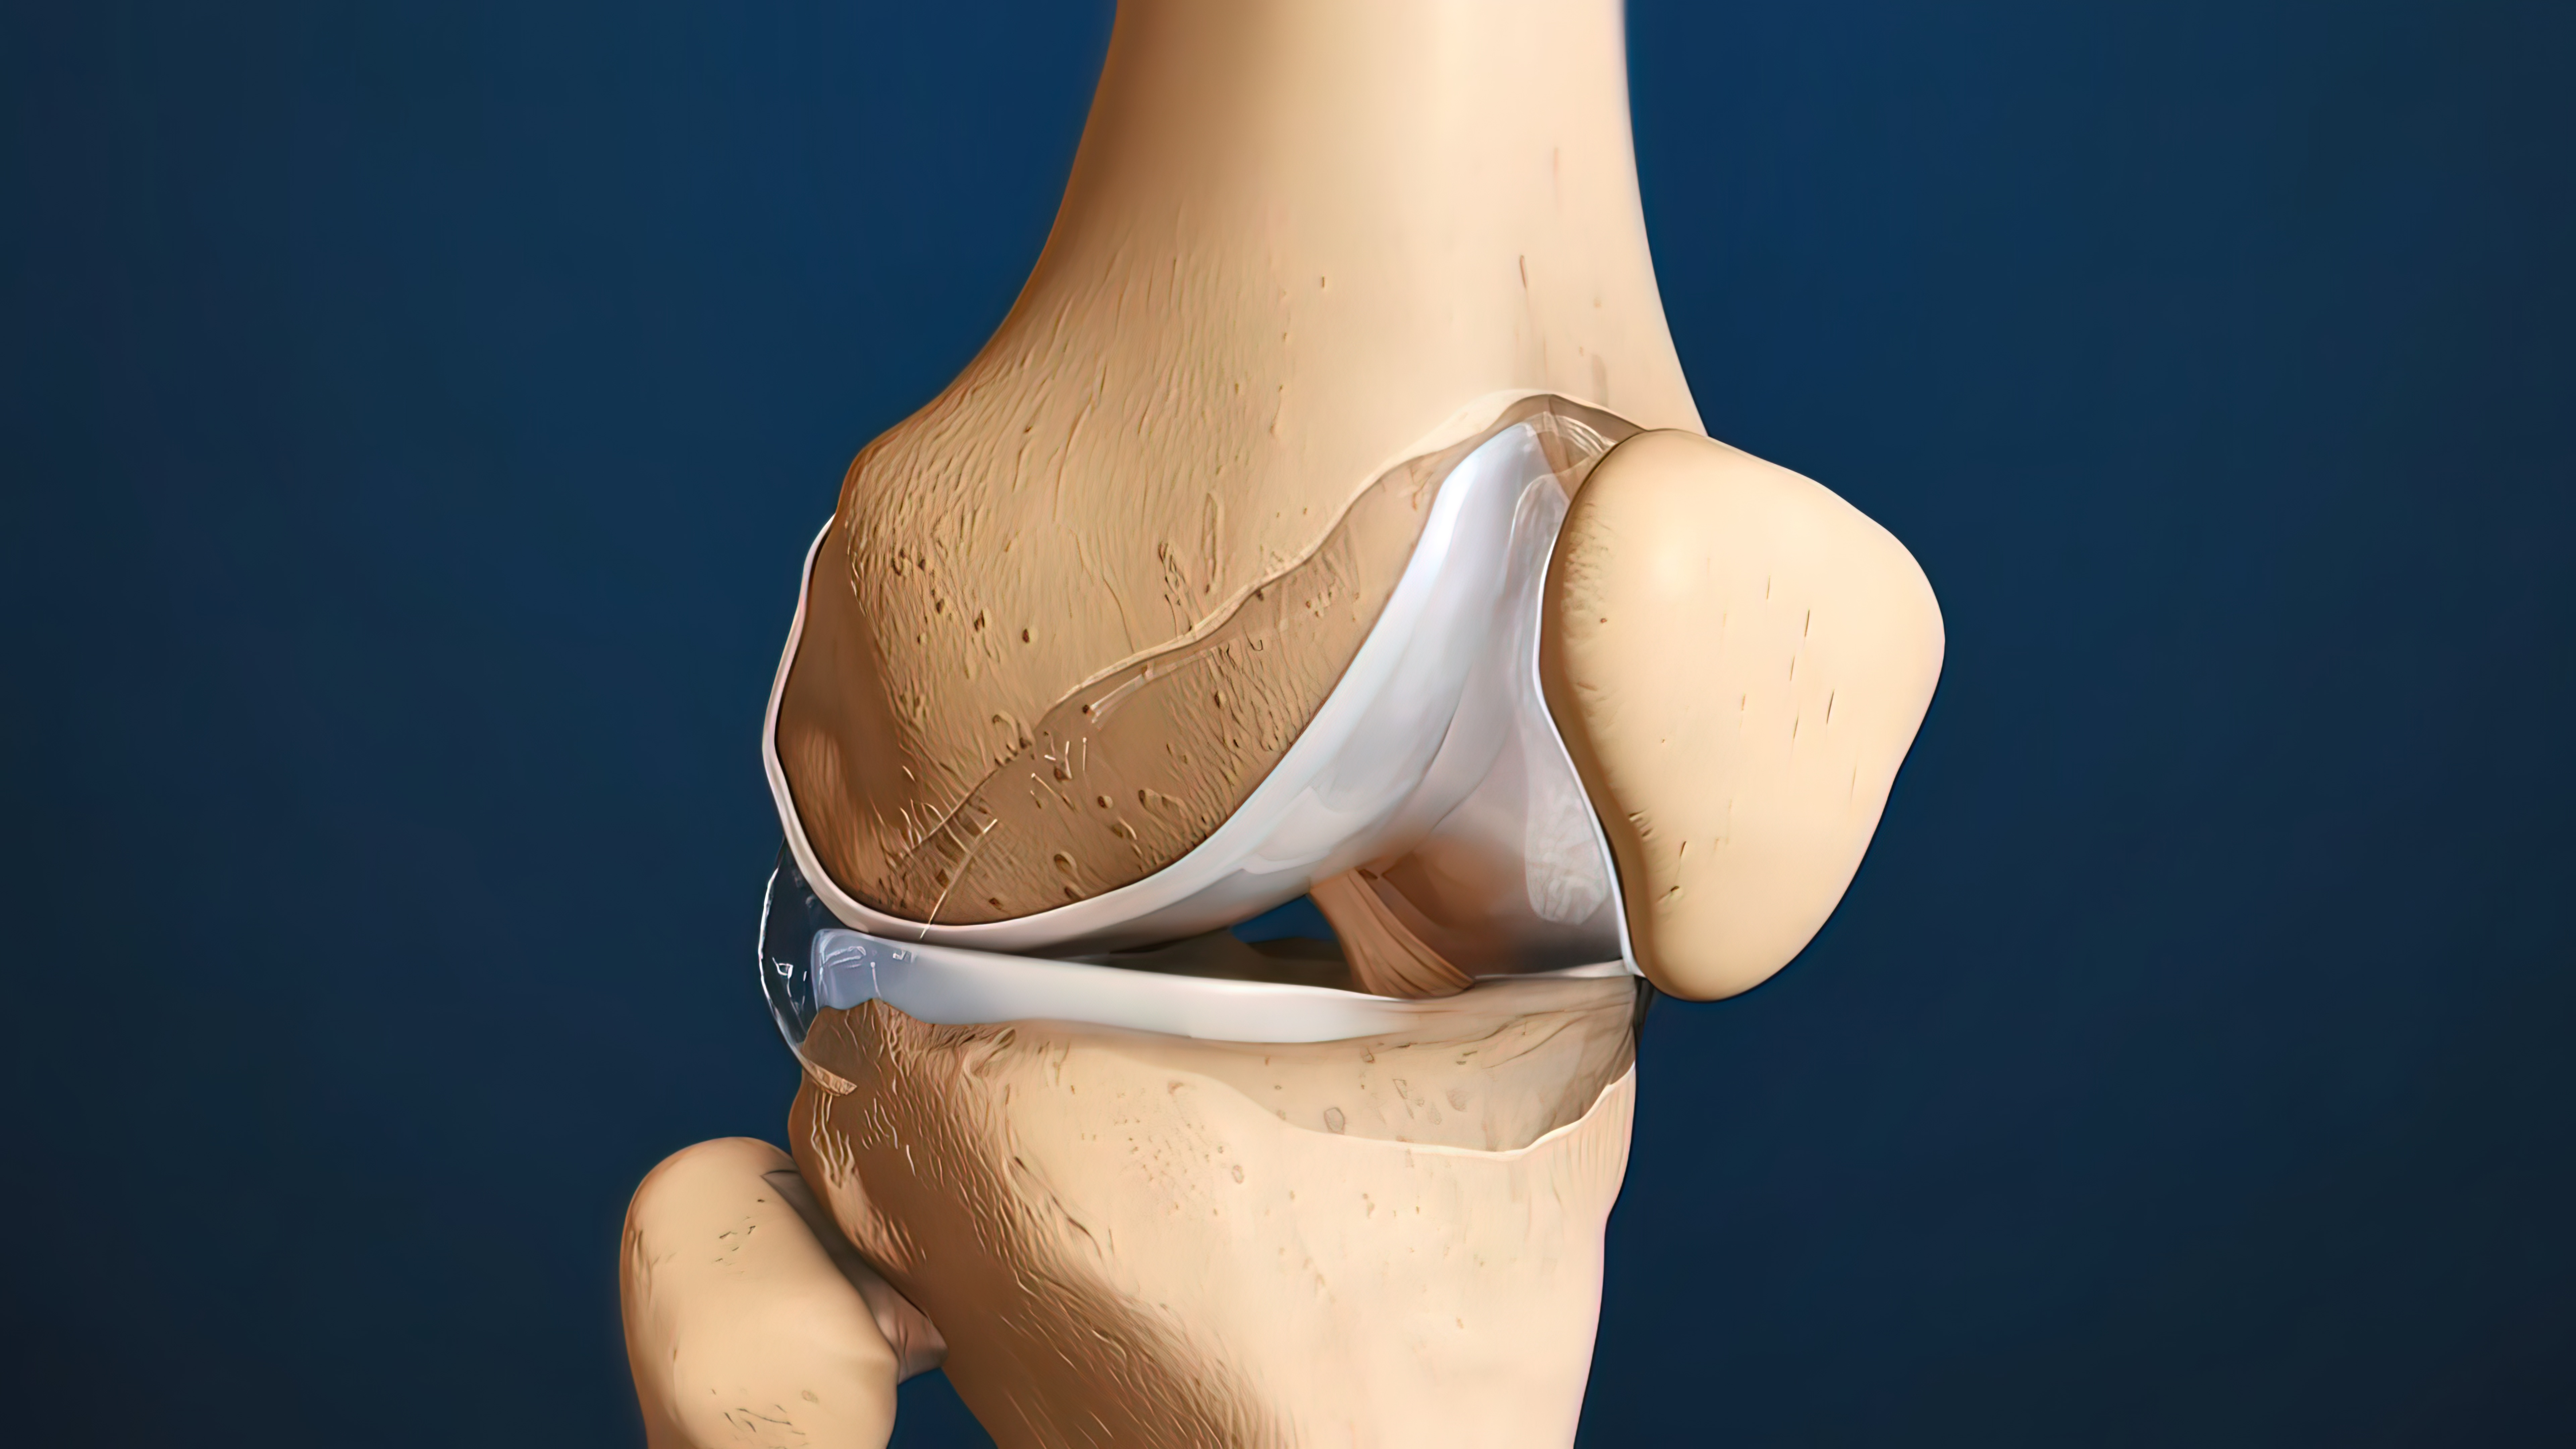

术后康复:膝关节屈曲90°活动受限的原因?